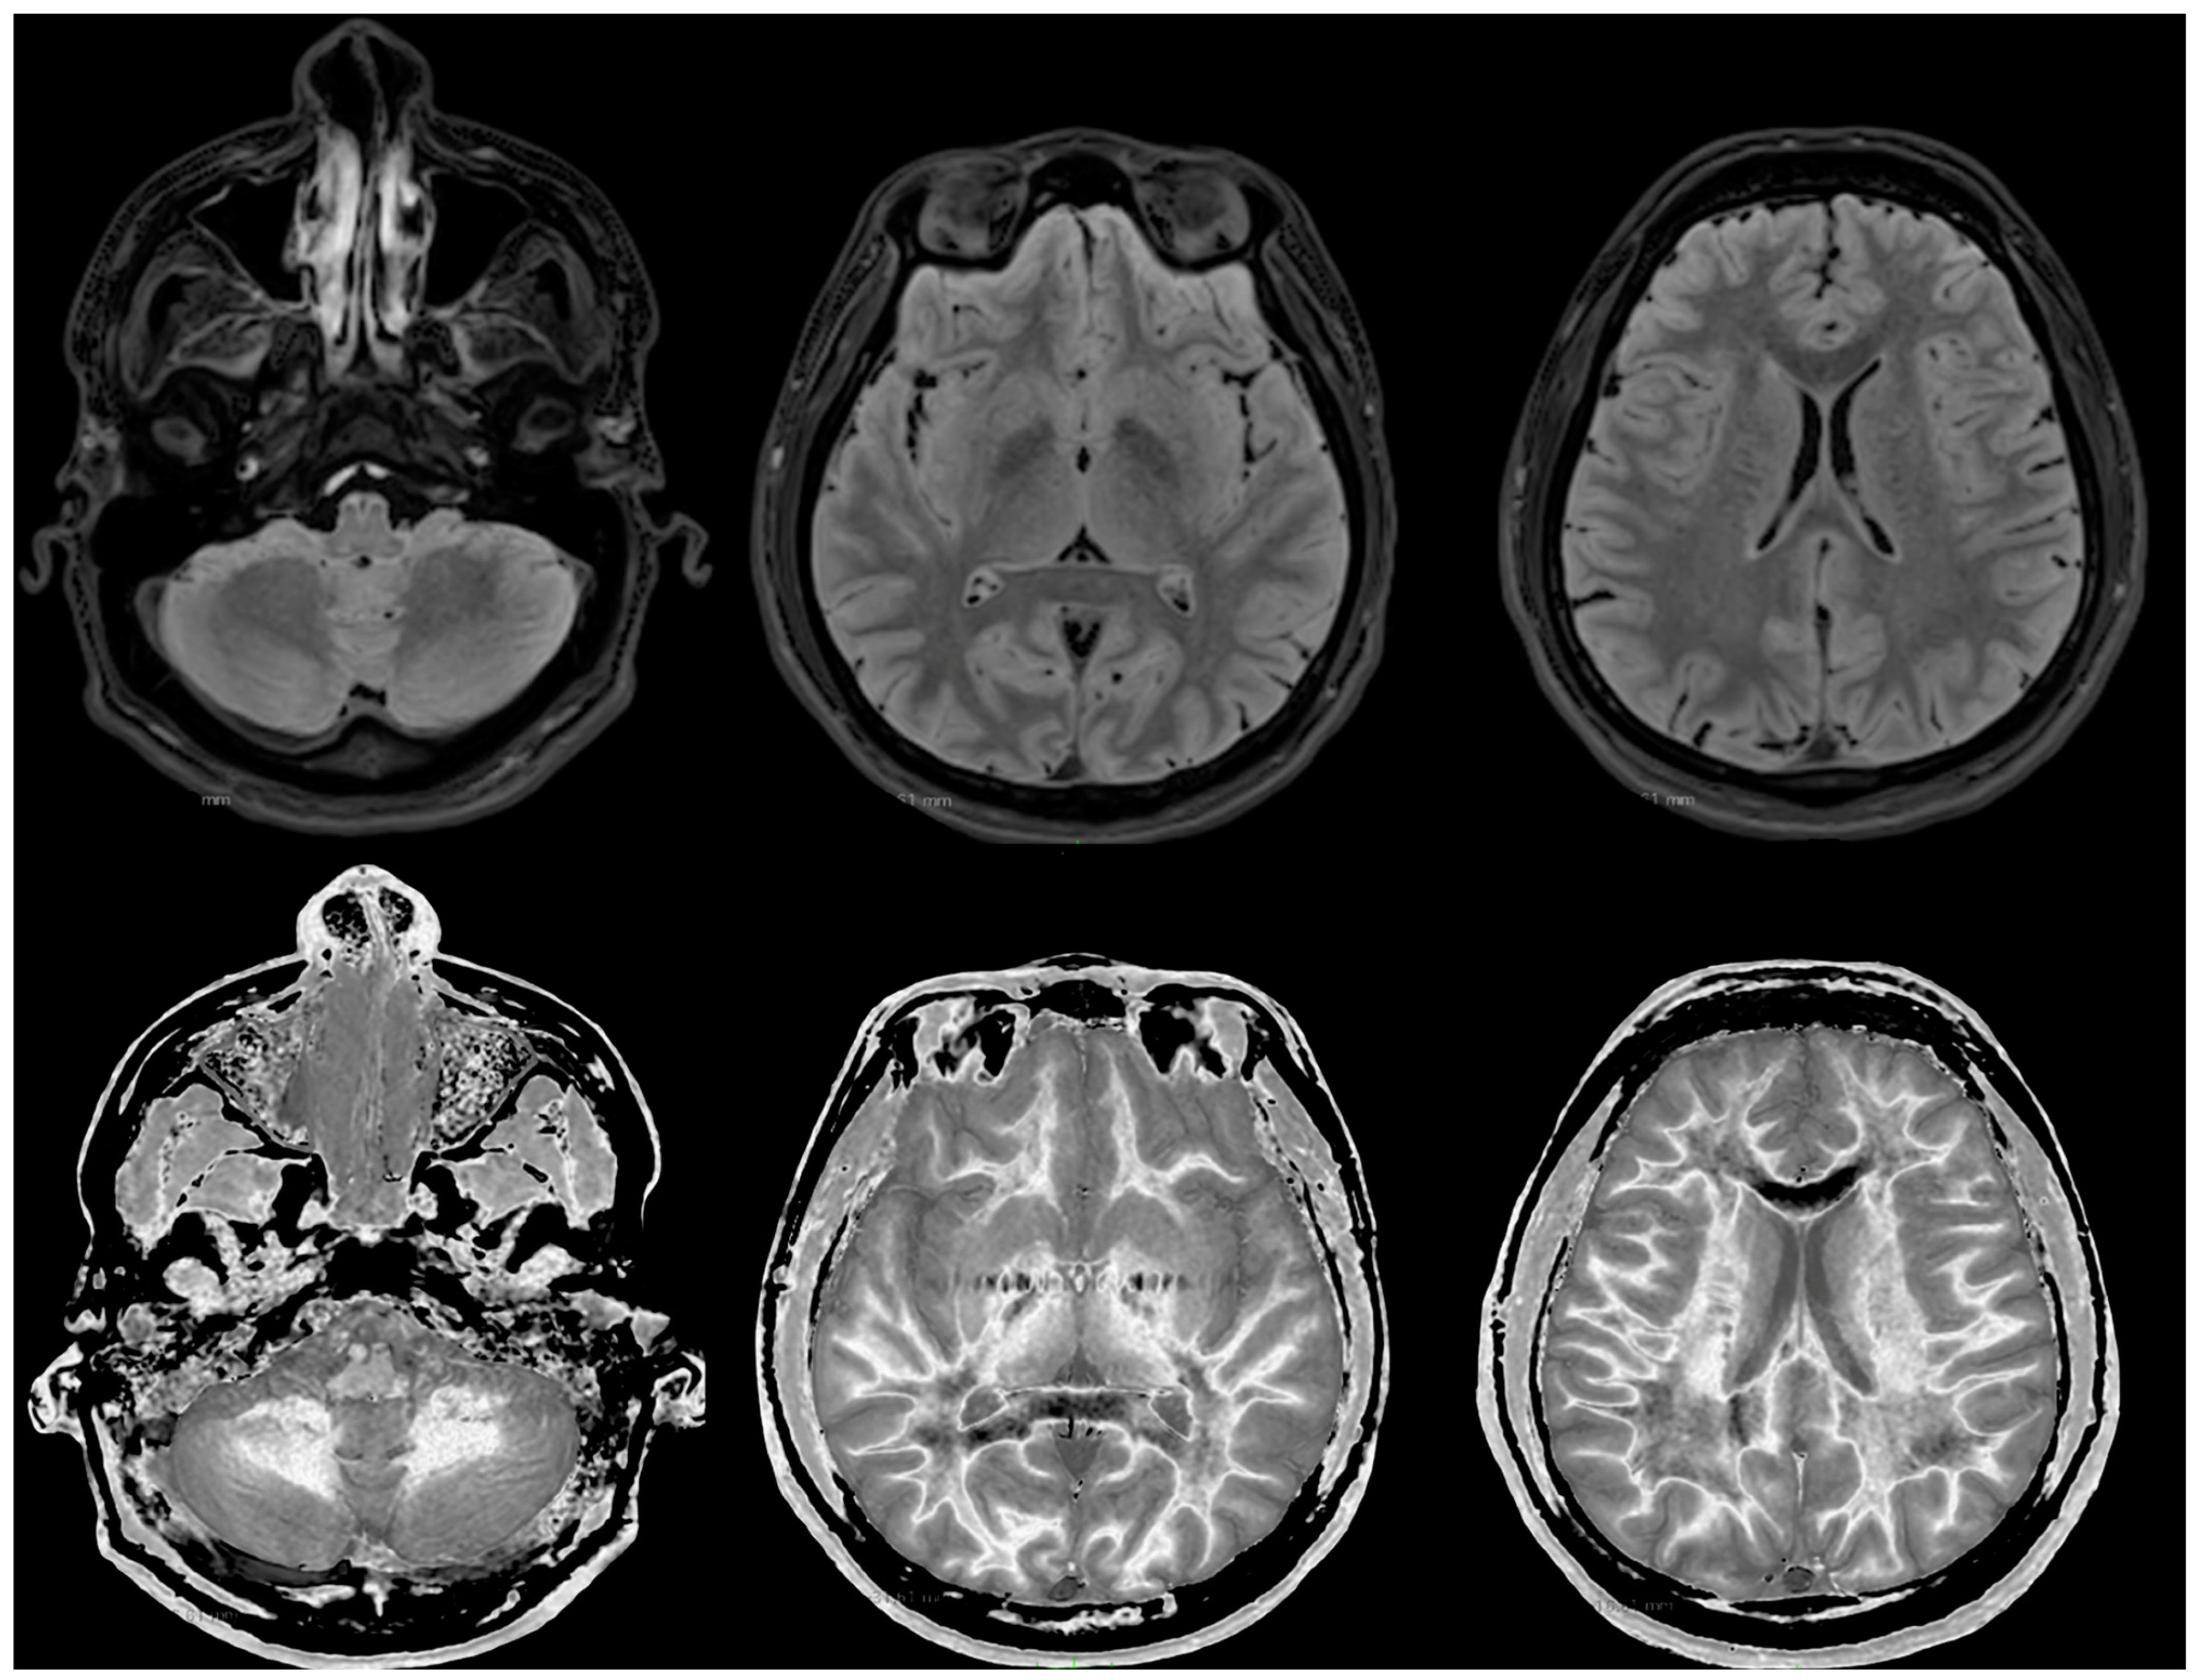

Figure 3 shows narrow mD dSIR images from the normal 18-year-old volunteer. His white matter is normal and shows a low signal (dark) appearance with a mid-grey appearance in and around the corticospinal tracts. Normal high signal boundaries (white lines) are seen at junctions between white and grey matter.

Figure 3. Normal volunteer. Two-dimensional narrow mD dSIR images. The narrow mD dSIR images show normal white matter as a very low signal intensity (dark) except for intermediate areas in and around the corticospinal tracts. Normal high signal boundaries are seen at the junction between white matter and grey matter.